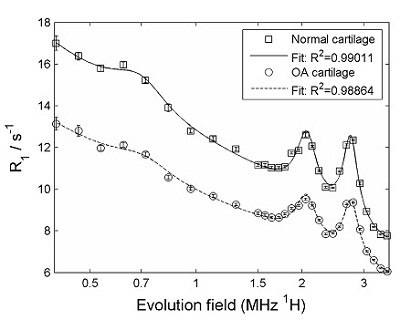

It is known that the concentration of proteins called glycans decreases in osteoarthritis. We are investigating whether FFC NMR relaxometry can detect differences in the measured quadrupole peaks, between normal and diseased joints, since the quadrupole peaks are strongly dependent on a tissue's immobile protein content. If so, FFC-MRI may be a viable method of detecting disease.

Relaxometry measurements of cartilage were carried out using our bench-top FFC NMR relaxometer. The figure below shows a comparison of R1 dispersion curves obtained from cartilage samples from normal and osteoarthritic patients - there is clearly a difference between the two.

FFC-NMR relaxometry on normal cartilage (squares) and cartilage from patient with osteoarthritis (circles). The difference between the two is clear. The data were further analysed by subtracting the "background" from the curves, in order to isolate the quadrupole peaks, as shown below.

The amplitude of the quadrupolar peaks is clearly reduced in the osteoarthritic cartilage.